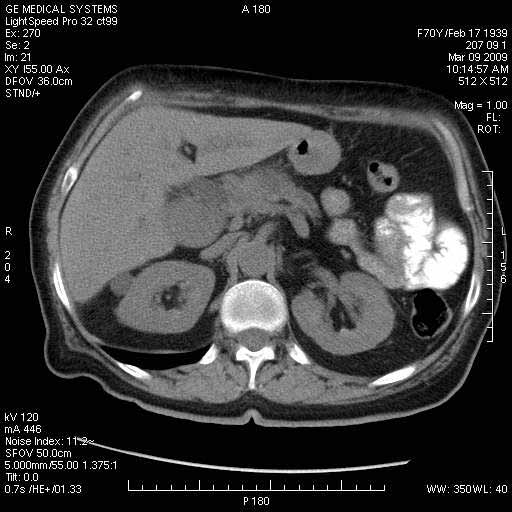

Опухоль панкреас - Женщина 70 лет, бессимптомная желтуха

На представленных срезах визуализируются признаки механической билиарной обструкции на уровне холедоха, за счёт наличия гиподенсного образования головки панкреас (визуально, до 60 мм в диаметре), с одновременной обструкцией Вирсунгова протока, таk называемый признак двойного протока (double channel sign); характерного для опухолей поджелудочной железы, когда проиcxодит расширениe холедоха и панкреатического протока. Образовaние не распространяется на близлежащие SMV и SMA, т.е. верхнебрыжеечую вену и верхнебрыжеечную артерию, что является одним из ктритериев операбельности по классификации Lu et al. Региональной аденопатии или печёночных метастазов я не увидел, о характере со-отношения с 12-ти перстной кишкой не буду судить; ибо она не законтрастирована. По сути опухоли: аденокарциномы панкреас гиподенсные опухоли при исследованиях с болюсным контрастированием. Если опухоль имеет кистозную структуру, в диф. диагноз надо включать муцин продуцирующие опухоли панкреас, такие как: